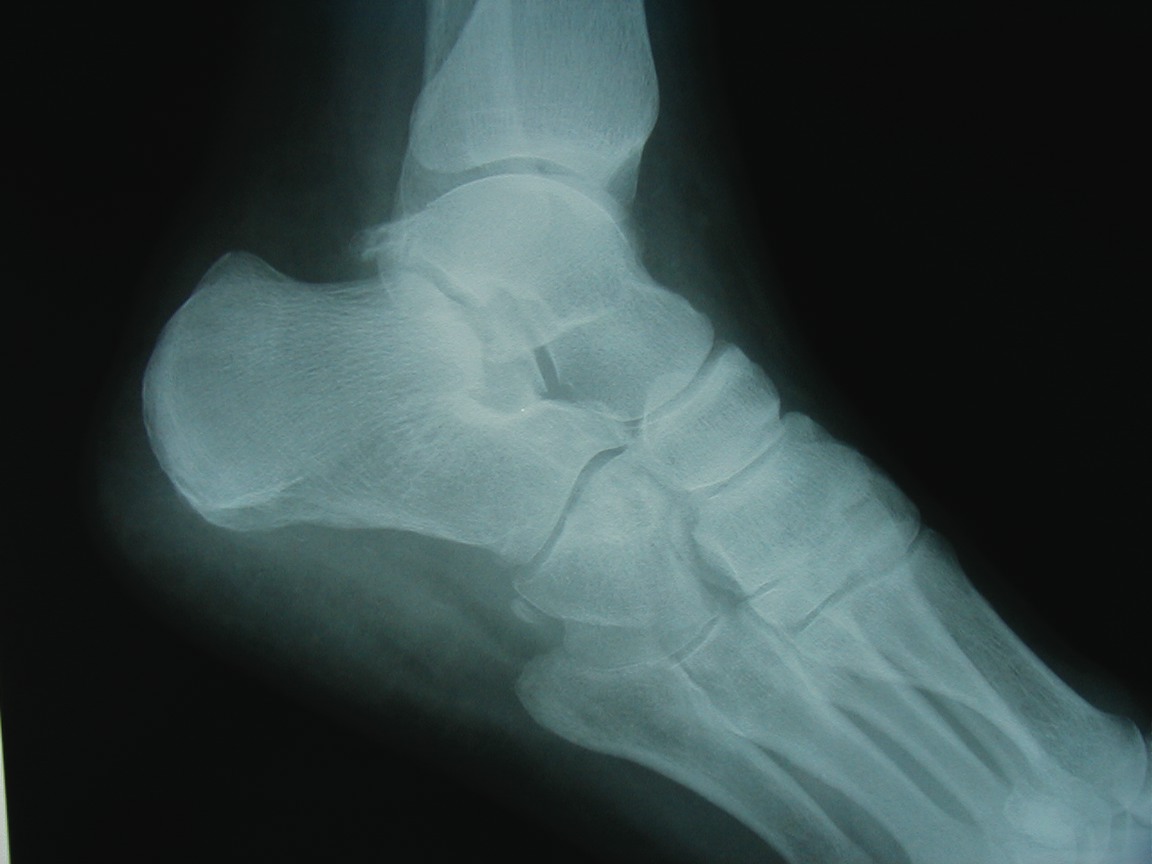

Adult-acquired flatfoot (AAF) is one of the more common conditions that podiatrists see in practice. With this in mind, some of the leading experts on this subject shared their views and experience on this subject. They discuss the role of diagnostic imaging, their use of conservative treatments and their perspectives on appropriate surgical procedures. Without further delay, here is what they had to say. Q: What ancillary studies are required for proper diagnosis and treatment selection for the adult-acquired flatfoot? A: Michael S. Lee, DPM, says AAF is generally a clinical diagnosis. Other than the physical exam, Shannon Rush, DPM, says a proper radiographic evaluation is the most important aspect of diagnosing AAF and arriving at an appropriate course of treatment. Dr. Rush emphasizes the inclusion of foot and ankle views as well as hindfoot alignment and long leg calcaneal views. All the panelists agree that neutral position X-rays are helpful in determining the degree of the deformity and what procedure one should perform. Alan Catanzariti, DPM, says it is important to evaluate the talus-first metatarsal angle on both AP and lateral radiographs. He adds that the AP views also enable one to see the amount of talar head that is covered by the navicular. Standard radiographs also allow clinicians to assess the tritarsal complex for degenerative changes, according to Dr. Catanzariti. He says these degenerative changes may indicate an arthrodesis procedure as opposed to performing reconstructive osteotomies or soft tissue procedures. The majority of the panelists recommend obtaining ankle X-rays in order to detect valgus deformity within the ankle. When there is valgus deformity within the ankle joint, Dr. Catanzariti will typically consider performing a medial displacement osteotomy of the calcaneus. “This helps decrease the tension within the deltoid ligament and prevent further attenuation of medial soft tissue structures,” explains Dr. Catanzariti. In cases of end-stage flatfoot deformity, Jordan Grossman, DPM, says AP ankle views are useful in evaluating for deltoid ligament insufficiency and valgus deformity of the talus within the ankle mortise. Gerard V. Yu, DPM, and Dr. Catanzariti agree with Dr. Rush about the value of obtaining long leg axial films. Dr. Catanzariti says long leg axial views and Saltzman views allow one to evaluate the calcaneus, subtalar joint, ankle joint and tibia relative to one another. He adds that these views often facilitate appropriate procedure selection. Lower-extremity alignment views may also be indicated in certain instances, according to Dr. Rush. Dr. Grossman concurs, noting that obtaining Cobey and hindfoot alignment views are useful in severe cases and with lower-extremity deformity. When it comes to magnetic resonance imaging (MRI), Dr. Rush says he “rarely, if ever” uses it in his workup for AAF. Dr. Catanzariti agrees. However, if he is contemplating arthrodesis versus reconstruction, Dr. Catanzariti will sometimes obtain a MRI in order to detect early degenerative changes within the subtalar joint that are subtle on standard X-rays. Dr. Grossman concurs, noting that MRI is indicated in “select circumstances” in which the diagnosis is unclear. Dr. Lee says one may employ MRI or ultrasound imaging to evaluate the posterior tibial tendon for attenuation or complete rupture. Dr. Yu emphasizes that MRI is most helpful when clinicians use a facility that has an experienced musculoskeletal radiologist, who is knowledgeable about the clinical entity and its primary and secondary manifestations. “I believe the MRI should be part of the standard workup for AAF if you plan to do direct surgical repair alone or as part of the correction of the deformity,” maintains Dr. Yu. Dr. Lee adds that a CT scan may have limited use in determining the degree of arthrosis in stage 3 or stage 4 deformities. Gait analysis may also be helpful in procedure selection, according to Dr. Catanzariti. Q: What is the significance of the posterior tibial tendon in the adult-acquired flatfoot? A: Dr. Yu says the primary purpose of the posterior tibial tendon is decelerating internal rotation of the tibia and accordingly limiting pronation of the foot following heel strike in gait. The intrinsic pathology specific to the posterior tibial tendon is “insignificant once the deformity has occurred,” notes Dr. Rush. He says the most important overriding factor is that the tendon has functionally weakened and is unable to stabilize the midtarsal joint. Dr. Rush says this functional weakness may be due to posterior tibial tendon dysfunction (PTTD) or subluxation in the rearfoot. The posterior tibial tendon plays “a primary role in the development of AAF,” according to Dr. Grossman. Dr. Lee says the posterior tibial tendon plays an important role early in the process but its importance diminishes as the deformity progresses. He notes the spring ligament may become attenuated in some situations. While there are several possible causes of AAF, Dr. Grossman says insufficiency or rupture of the posterior tibial tendon is the most common cause. The posterior tibial tendon often may be attenuated or diseased in AAF, according to Dr. Catanzariti, but he says this can vary from patient to patient. If patients have significant symptoms as a direct result of disease within the posterior tibial tendon, Dr. Catanzariti says they may require surgical intervention, which could include a tenosynovectomy, a partial tendon debridement or actual resection of an attenuated tendon. He notes these interventions may be supported by tendon transfers. In these cases, Dr. Catanzariti prefers a flexor digitorum longus tendon transfer. Dr. Rush says the clinical view of the posterior tibial tendon or its appearance on MRI does not influence one particular reconstruction over another. When it comes to stage 3 and stage 4 AAF, Dr. Lee says the posterior tibial tendon plays little importance in function, diagnosis or surgical treatment selection. If a patient has a predisposition to excessive pronation due to a specific foot structure, Dr. Yu says the posterior tibial tendon is “very significant.” When patients have a cavus foot, he notes the inherent stability of the foot will limit pronation. However, if a patient has hypermobile joint laxity syndrome, Dr. Yu says the posterior tibial tendon will be more important as it will “work harder to prevent excessive pronation.” If one stabilizes the foot well with osseous procedures, especially fusions, the importance of the posterior tibial tendon for function decreases, according to Dr. Yu. When one performs a posterior tibial tendon transfer for other conditions (i.e., dropfoot deformity), Dr. Yu says the foot structure remains the same due to the inherent interlocking of osseous units. When performing a triple arthrodesis, Dr. Yu notes the surgeon can leave the PT tendon alone altogether unless the pain there is due to active inflammation around the tendon itself. In essence, the more inherently stable the foot is, whether by surgical fusion or anatomical stability, the less important the PT tendon is to overall foot function. Q: What conservative measures have been successful in your hands in the treatment of AAF? A: Employing orthotics in combination with antiinflammatory medications and posterior muscle group stretching provides relief in milder cases of AAF, according to Dr. Catanzariti. When it comes to stage 1 conditions, Dr. Lee notes he has had a fair amount of success utilizing figure-of-eight ankle braces along with rest, ice, NSAIDs and shoe gear modifications. He notes that stage 2 deformities have responded well to prefabricated and custom orthotics, rest, activity modification and NSAIDs. Dr. Lee has also utilized ankle foot orthoses (AFOs). Depending on the presentation and degree of the deformity, Dr. Grossman says he has had success with the aforementioned modalities as well as physical therapy, cast immobilization and a removable walking boot. Functional orthotics may be helpful in the early stage of AAF but Dr. Yu says he generally does not use them. Dr. Yu notes that some companies make a variety of orthotic devices that “are too flimsy and do not have enough substance to do the job.” Essentially, one needs to ensure bracing of the foot to the leg, according to Dr. Yu, especially in the presence of other factors like obesity, genu valgum, etc. Dr. Yu says Aircast ankle braces and similar devices may provide good relief prior to using the more sophisticated and expensive devices like the Richie Brace and AFOs. With chronic conditions, Dr. Rush will use aggressive custom orthoses, Richie Braces and the Arizona AFO prior to surgical intervention. With stage 3 and stage 4 deformities, Dr. Lee will brace them with either UCBL orthotics or AFOs. If these fail, he proceeds to surgical intervention. The other panelists concur that one can use conservative bracing for stage 3 and stage 4 deformities in patients who are not surgical candidates. In these patients, Dr. Rush has had success with the Arizona AFO while Dr. Catanzariti has utilized supramalleolar AFOs with good results. In regard to conservative therapy, Drs. Rush and Yu say there are many factors to consider including the patient’s level of activity, weight loss, patient education, proper shoe gear and rehabilitation. Realistic expectations are essential and become more important as patients progress from stages 1 to 4, according to Dr. Yu. He says a patient with stage 3 or 4 deformity and low activity may respond surprisingly well to bracing but bracing is unlikely to be successful in a highly active patient with stage 2 AAF. Q: At what point does AAF become a surgical foot? A: The majority of the panelists consider surgical treatment when the deformity is progressive, grossly unstable and doesn’t respond to functional bracing. Dr. Rush says the potential progression of the deformity is a significant concern. “Severe talonavicular and subtalar subluxation can have a devastating influence on the ankle joint,” emphasizes Dr. Rush. “If the lateral peritalar drift is left unabated, the ankle can also fall into valgus.” Dr. Lee says he performs surgery for end-stage deformities such as stage 3 and stage 4 conditions. However, Dr. Yu notes that even severe deformities do not justify surgery alone. “If the other foot is flat and asyptomatic, you may be able to manage the pathologic foot without surgery,” points out Dr. Yu. If bracing fails, one needs to turn to surgical options, according to Dr. Yu. He emphasizes that physicians should always remember to treat patients in conjunction with their disease or deformity and not the X-rays. He notes that clinical correlation is essential to effective treatment. Q: When are calcaneal osteotomies indicated in the treatment of AAF? A: Dr. Yu says these procedures are “rarely” indicated for treating AAF. He believes this approach has been abused in an attempt to avoid more time-tested techniques, such as the gold standard triple arthrodesis, especially in the later stages of AAF when the deformity can be quite severe. In his experience, Dr. Yu says the calcaneal osteotomy has little impact in resolving severe AAF “when a fusion in conjunction with tibialis posterior repair and posterior lengthening would have worked out better.” While he notes that calcaneal osteotomies are very helpful in the earlier stages of the disease, Dr. Yu emphasizes that many of these patients will do well without surgery. Drs. Grossman, Catanzariti and Lee believe calcaneal osteotomies are primarily indicated for flexible or reducible deformities. These procedures allow surgeons to correct various deformities while maintaining midtarsal and subtalar joint motion, according to Dr. Grossman. He says this will “most likely decrease the likelihood of adjacent joint demand and arthrosis that one commonly sees with an isolated or triple arthrodesis.” Citing the versatility of calcaneal osteotomies, Dr. Catanzariti calls them an excellent alternative to arthrodesis procedures. “These osteotomies spare the tritarsal complex and allow the hindfoot to function in a relatively normal fashion,” explains Dr. Catanzariti. Dr. Lee concurs. If the flatfoot is supple, he says one can achieve correction with calcaneal osteotomies while preserving most of the hindfoot motion. When it comes to late stage 1 AAF, Dr. Catanzariti will consider posterior calcaneal displacement osteotomies and sometimes uses this approach to treat early stage 2 conditions. Dr. Lee utilizes posterior calcaneal displacement osteotomies for early stage 2 AAF and employs the Evans calcaneal osteotomy and double osteotomies for late stage 2 conditions. For mid- to late stage 2 AAF, Dr. Catanzariti considers performing an anterior open wedge osteotomy in combination with a posterior displacement osteotomy. Dr. Rush says calcaneal osteotomies are a “wonderful surgical tool” for treating AAF. He performs a posterior osteotomy with any valgus malalignment of the subtalar joint when a subtalar arthrodesis is not indicated. Obtaining hindfoot alignment and long leg calcaneal axial views help in planning with this procedure, according to Dr. Rush. He maintains that clinicians must be careful to evaluate the midtarsal joint and medial column for instability and supinatus. In the presence of instability or deformity, Dr. Rush notes one must add ancillary procedures in order to stabilize the medial column. Dr. Rush adds that naviculocuneiform arthrodeses serve to stabilize the medial column and address the naviculocuneiform fault if one exists. Dr. Grossman says he typically performs calcaneal osteotomies in combination with other bony and/or soft tissue procedures. Dr. Rush does not utilize an isolated anterior calcaneal osteotomy for AAF. He says one must combine this procedure with the posterior osteotomy to correct the valgus and lateral translation in the subtalar joint. Dr. Rush strongly emphasizes paying close attention to the subtalar alignment when selecting these procedures. Dr. Lee also notes that he prefers calcaneal osteotomies over isolated hindfoot fusions when treating AAF in smokers, more active patients and those with a normal or slightly elevated body mass index (BMI). Q: When is an isolated or combined joint arthrodesis indicated in treating AAF? A: According to Dr. Yu, these procedures are indicated when there is significant deformity with significant disability and symptoms, especially in cases that involve degenerative arthritis or excessive mobility that cannot be predictably controlled by other means. When one considers performing three joint preservation procedures, Dr. Yu believes one joint fusion can achieve the same outcome. He says performing an isolated joint fusion is especially beneficial for patients who have a low level of activity and want relief of their pain and a stable foot. If one achieves the fusion in a neutral position without varus or valgus, Dr. Yu says the fusion provides “exceptional functional outcomes” with minimal stress on adjacent joints, which minimizes the risk of subsequent degenerative joint disease. “It’s all about the alignment and position of fusion,” emphasizes Dr. Yu. Over the years, Dr. Yu notes anecdotally that he has observed, examined and analyzed a large number of adult patients who had congenital coalitions, realizing they had minimal to no symptoms until their late 40s and 50s or even later. Dr. Yu says the position of the fusion is key to minimizing stress on adjacent joints and structures. Tarsal coalition patients who present early in life invariably have peroneal spastic flatfoot deformities, creating a completely different clinical problem, according to Dr. Yu. However, he emphasizes that the technique one uses to perform these fusions is important. Rigid deformities, a degenerative midtarsal or subtalar arthritis are the primary indications for using isolated or combined arthrodesis procedures, according to Dr. Grossman. He says one may also consider these procedures for obese patients with AAF or in cases of underlying inflammatory arthritis. Dr. Grossman says he typically combines an isolated arthrodesis procedure with soft tissue reconstruction and posterior muscle group lengthening. As with all arthrodesis procedures, Dr. Grossman says the position primarily predicates outcomes and patient satisfaction. Dr. Lee utilizes isolated hindfoot fusions in late stage 2 deformities when there may be mild arthrosis in one or more of the hindfoot joints, when the deformity is severe on plain radiographs or in patients with a higher BMI. A subtalar joint arthrodesis may be effective in the presence of isolated subtalar joint disease or arthritis, according to Dr. Catanzariti, but he rarely uses this procedure to treat AAF. In these cases, Dr. Catanzariti prefers a double calcaneal osteotomy for stage 2 AAF, a triple arthrodesis for stage 3 AAF and a combination of triple arthrodesis and posterior calcaneal displacement osteotomy for stage 4 AAF. On the other hand, Dr. Lee says he tends to perform an isolated subtalar joint arthrodesis in many cases of AAF but will occasionally opt for talonavicular arthrodesis in more severe cases of AAF with significant talar declination. Dr. Rush notes that painful degenerative joints and significant subluxation in the subtalar or talonavicular joints are general indications for arthrodesis. Arthrodesis of the non-essential medial column joints, such as the naviculocuneiform or metatarsocuneiform joints, can easily and effectively stabilize the medial arch, according to Dr. Rush. He adds that combining this procedure with calcaneal osteotomies can “correct most degrees of instability.” While distraction fusions are effective for lateral peritalar subluxation, Dr. Rush cautions that they often do not address the valgus or translation in the subtalar joint. According to Dr. Lee, distraction arthrodesis of the calcaneocuboid joint is a powerful procedure but does have “some elevated risk of non-union.” In the presence of supinatus or varus deformities, all the panelists agree that one must perform some type of ancillary medial column procedure, whether it is a medial column fusion or an osteotomy. Dr. Mendicino is Chief of the Division of Foot and Ankle Surgery at the Western Pennsylvania Hospital in Pittsburgh. He is a Fellow and Past President of the American College of Foot and Ankle Surgeons, and is a Clinical Professor of Surgery at the Western Campus of the Temple University School of Medicine. Dr. Catanzariti is the Director of the Residency Training Program within the Division of Foot and Ankle Surgery at the Western Pennsylvania Hospital in Pittsburgh. He is a Fellow of the American College of Foot and Ankle Surgeons. Dr. Grossman is Chief of the Section of Podiatry at Akron General Medical Center in Ohio. He is a Fellow of the American College of Foot and Ankle Surgeons, and a Diplomate of the American Board of Podiatric Surgery. Dr. Lee is a Fellow and serves on the Board of Directors of the American College of Foot and Ankle Surgeons. He is a Diplomate of the American Board of Podiatric Surgeons. He recently chaired the adult flatfoot panel and co-authored the ACFAS Clinical Practice Guidelines for Adult Flatfoot. He is in private practice at Central Iowa Orthopedics in Des Moines, Iowa. Dr. Rush is a Fellow of the American College of Foot and Ankle Surgeons. He is a Staff Surgeon within the Department of Orthopedics at Kaiser Permanente in Walnut Creek, Ca. Dr. Rush is also a Staff Surgeon with the San Francisco Bay Area Foot and Ankle Residency Program. Dr. Yu is the Director of the Podiatric Surgical Residency Program (PSR-36) and is the Chief of the Section of Podiatry of the Division of Orthopedic Surgery at the St. Vincent Charity Hospital, and at the Huron Hospital in Cleveland. He is a Fellow of the American College of Foot and Ankle Surgeons, and is a Diplomate of the American Board of Podiatric Surgery. Dr. Yu is also the Director of Program Development and a faculty member of the Podiatry Institute.